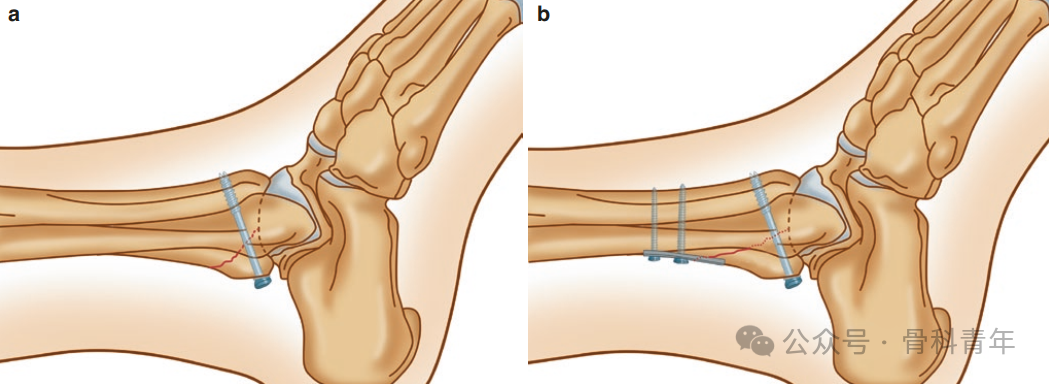

40%以上的踝关节骨折合并后踝骨折,对踝关节骨折,通常认为累及25%关节面的后踝骨折需手术干预。除后踝钢板外,后踝骨折螺钉内固定主要有间接复位前向后螺钉固定与后外侧入路切开复位后向前螺钉固定两种方法:

• 前向后螺钉术中无需翻身便于手术操作,但无法直视下复位后踝,导针置入时无法精准判断位置;

• 后向前螺钉需漂浮体位或仰卧位,操作繁琐;但可在直视下复位,且生物力学研究上,后前螺钉比前后螺钉具有更强的稳定性。

后向前螺钉的置入存在置入下胫腓间隙、激惹踇长屈肌腱及损伤腓肠神经的风险。为避免上述问题,有学者进行了相关标本研究,以明确后踝螺钉置入的安全区